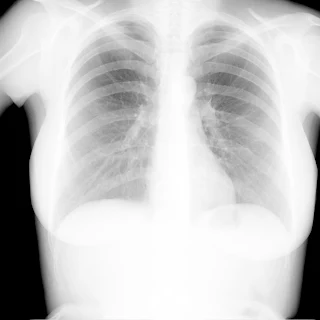

Флюорограма №12

Легені без вогнищево - інфільтративних змін. Корені не змінені. Синуси вільні. Серце норма.